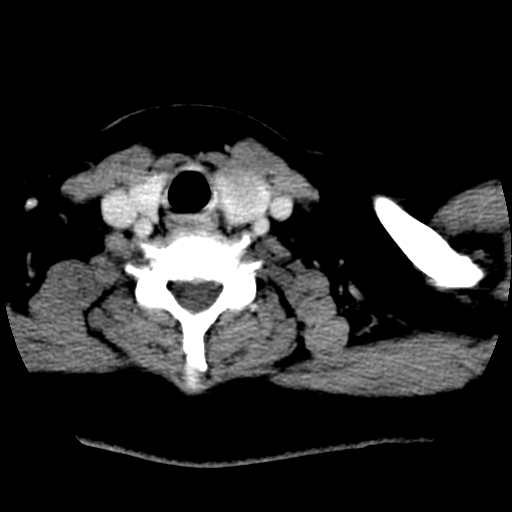

标题: CT25491:女,55岁,发现左侧甲状腺肿块一个月。 [打印本页]

标题: CT25491:女,55岁,发现左侧甲状腺肿块一个月。

女,55岁,发现左侧甲状腺肿块一个月,彩超示:甲状腺多发结节伴左叶结节液化。

左右叶都有,峡部也受累,有钙化,考虑结甲可能性大。

考虑右叶结节性甲状腺肿,伴左叶钙化。主要(1)密度均匀,边境清。(2)病灶与血管界限清。